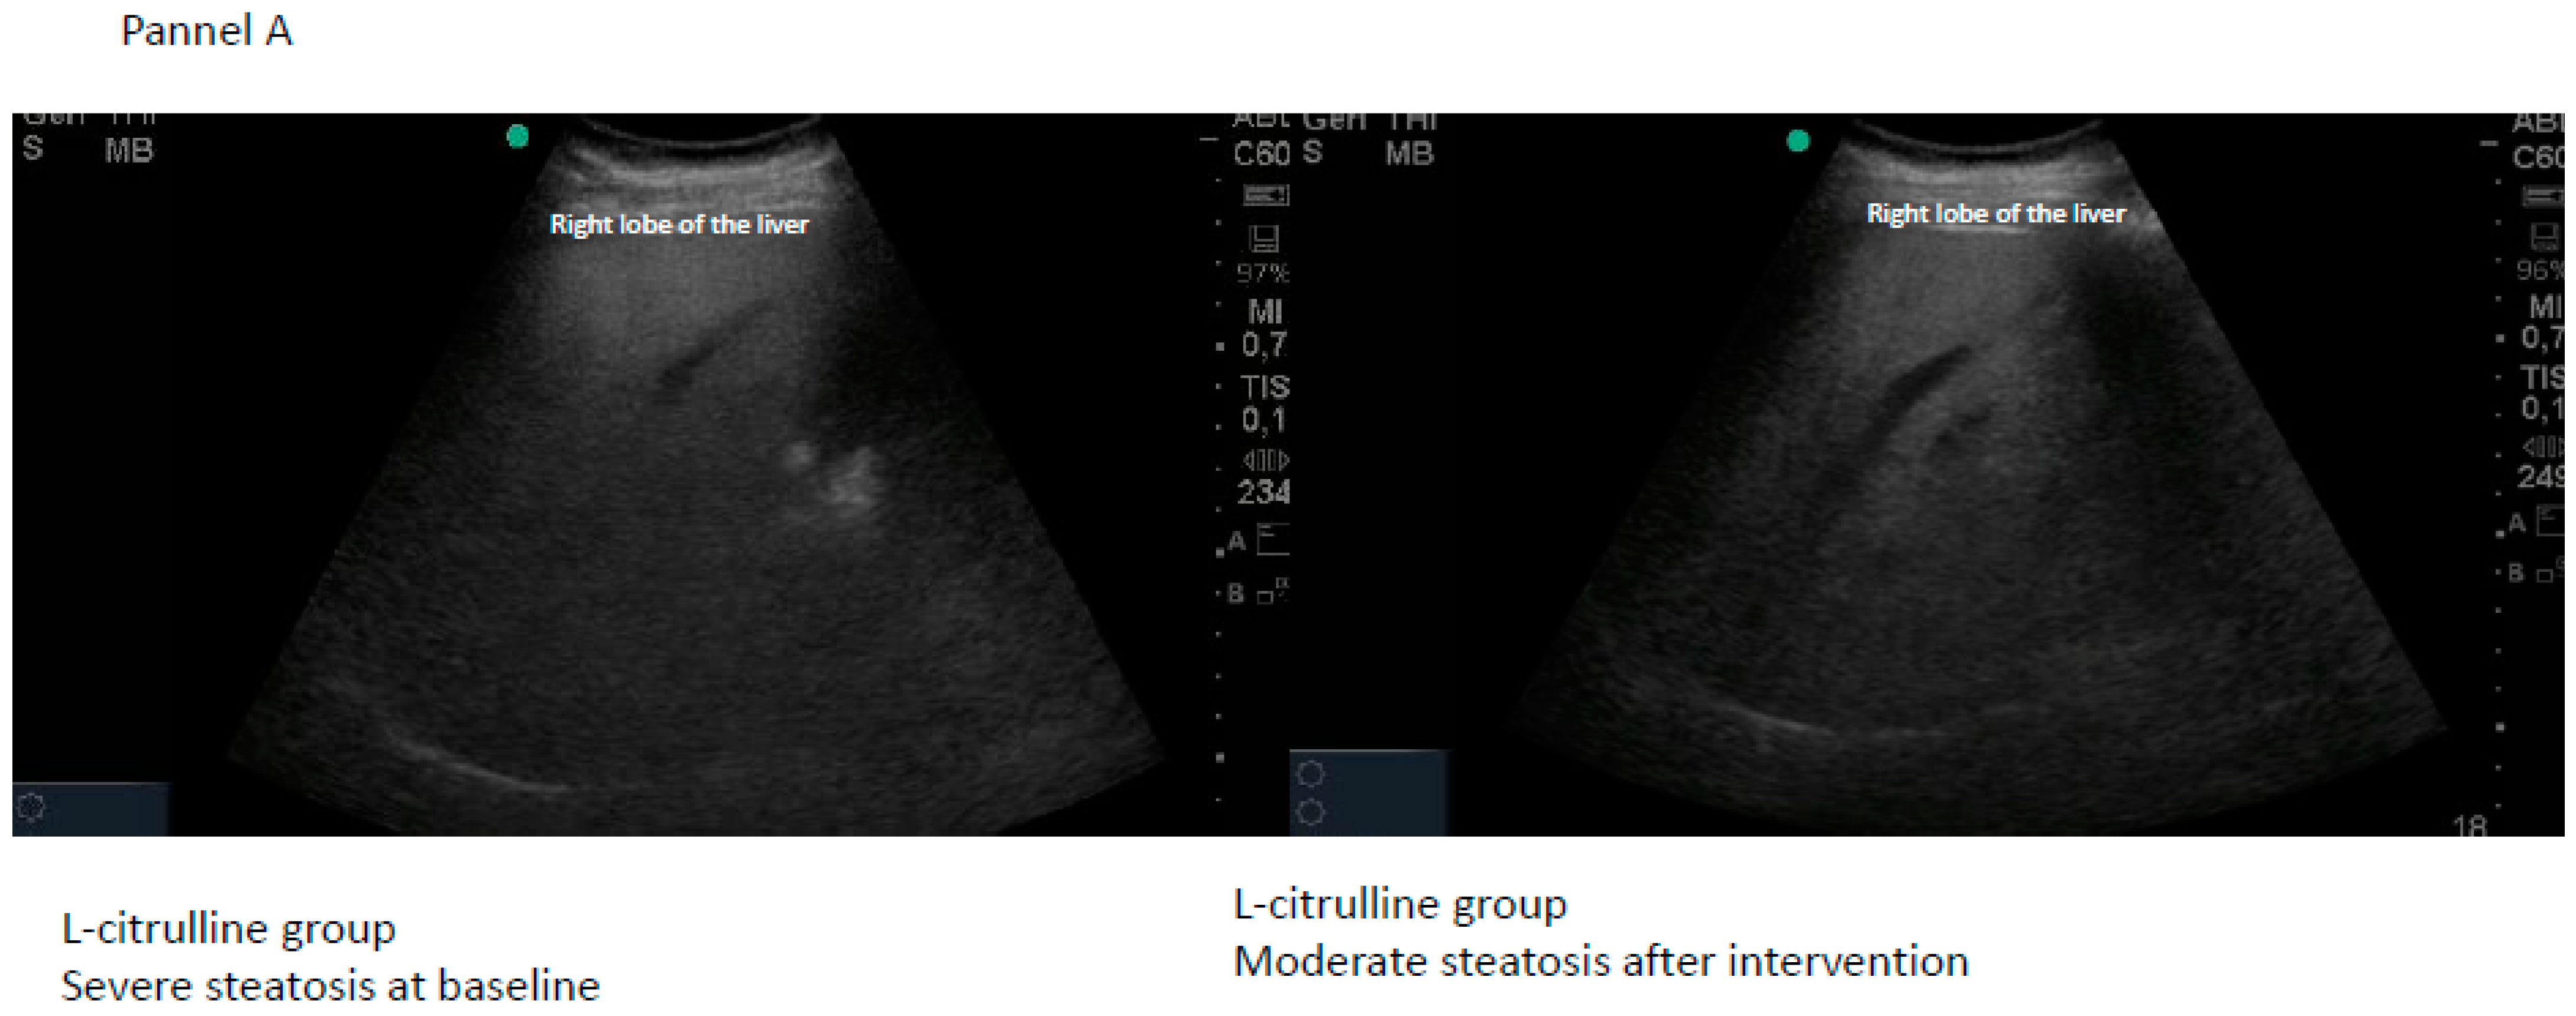

| Citrulline | Final Steatosis | |||||||

|---|---|---|---|---|---|---|---|---|

| n = 22 | Normal | Mild | Moderate | Severe | Total | Chi-Square | p | |

| Baseline steatosis | Mild | 8 | 2 | 0 | 0 | 10 | 11.589 | 0.0007 |

| Moderate | 1 | 1 | 6 | 0 | 8 | |||

| Severe | 0 | 0 | 2 | 2 | 4 | |||

| Total | 9 | 3 | 8 | 2 | 22 | |||

| Placebo | Final steatosis | |||||||

| n = 20 | Normal | Mild | Moderate | Severe | Total | Chi-square | p | |

| Baseline steatosis | Mild | 3 | 3 | 0 | 0 | 6 | 1.633 | 0.2013 |

| Moderate | 3 | 3 | 6 | 0 | 12 | |||

| Severe | 0 | 0 | 1 | 1 | 2 | |||

| Total | 6 | 6 | 7 | 1 | 20 | |||